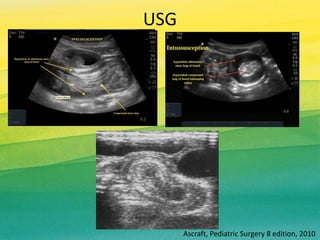

USG

Ascraft, Pediatric Surgery 8 edition, 2010